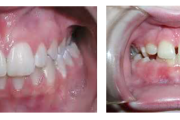

Turritavad ülemised lõikehambad.

Ülemise hambakaare kitsenemine ehk tagumiste hammaste risthambumus.

Ruumipuudus eesmiste hammaste osas